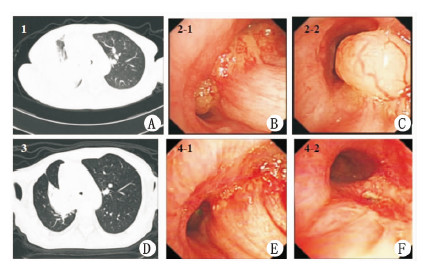

例1 患者女性,41岁,因“痰中带血1年,加重伴气急2个月”于2011 年11 月20 日入住邵逸夫医院。患者1年前确诊肺腺癌,拒绝手术及放化疗,长期口服中药。2个月前气急进行性加重,不能平卧。体格检查:呼吸促,右肺呼吸音低,左肺干啰音。胸部CT:右主支气管几乎完全闭塞,左主支气管开口腔内新生物,尚存狭小缝隙(图 1A)。纤维支气管镜:隆突黏膜浸润,右主支气管管腔堵塞,左主支气管腔内新生物,管腔明显狭窄,气管镜进入声门后十余秒,患者气急明显加重,不能耐受,遂停止检查。患者右主支气管完全闭塞,左主支气管亦严重狭窄,气管插管无法解决通气问题,遂选择行ECMO支持下经支气管镜支气管新生物切除术。患者取半卧位,采用股静脉-股动脉(V-A)模式,从右股静脉经皮穿刺置入F 22 号静脉插管引流,左股动脉经皮穿刺置入F16 号股动脉插管灌注。VA-ECMO启动后,立即静脉给予丙泊酚基础麻醉镇静,气管插管。循环系统预充:复方电解质注射液500 mL,高渗氯化钠羟乙基淀粉注射液200 mL,氨甲环酸注射液200 mL;转流新鲜血浆240 mL,红细胞2 U,肝素4 mg/kg,转流中监测平均动脉压(MAP)、SpO2。血流速度为2.5 L/min 左右,使SpO2保持在90% 以上。术中支气管镜示:右主支气管腔内新生物,隆突累及,右主支气管管腔基本堵塞,左主支气管腔内新生物,左主支气管管腔明显狭窄,左上下各段支气管管腔通畅,未见明显狭窄或新生物堵塞管腔(图 1BC)。予以左主支气管腔内肿块高频电圈套去除,根部予氩气刀治疗,过程顺利,治疗后左主支气管管腔基本通畅。遂停ECMO,鱼精蛋白中和肝素。待患者清醒后拔气管插管。患者术后胸闷气急明显好转,生命体征及SpO2平稳。给予埃克替尼靶向治疗肺癌,顺利出院,1个月后复查CT(图 1D)、气管镜(图 1EF)提示左主支气管管腔仍通畅。

图 1 A:术前胸部CT示,右肺肿块伴阻塞性肺炎,右主支气管几乎完全闭塞,左主支气管尚存狭小缝隙。图B:术前气管镜(隆突)示,右主支气管腔内新生物,隆突累及,右主管腔基本堵塞,左主可见新生物。图C:术前气管镜(左主支气管)示,左主支气管腔内新生物,左主支气管管腔明显狭窄。图D:术后胸部CT示,左主支气管狭窄较前明显好转。图E:术后气管镜(隆突),右主支气管仍几乎完全堵塞,左主支气管通畅。 图F:术后气管镜(左主支气管)示,左主支气管通畅,内侧壁新生物伴局部凹陷。